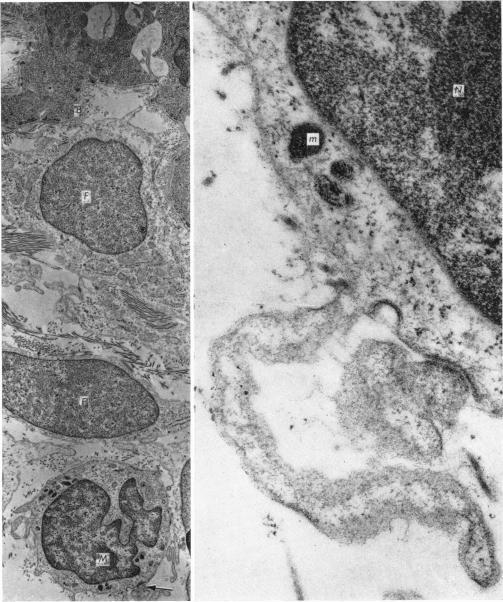

The ultrastructure of the skin of human embryos. 8. Melanoblast and intrafollicular melanocyte.

J Anat. 1971 Jan;108(Pt 1):99-108.